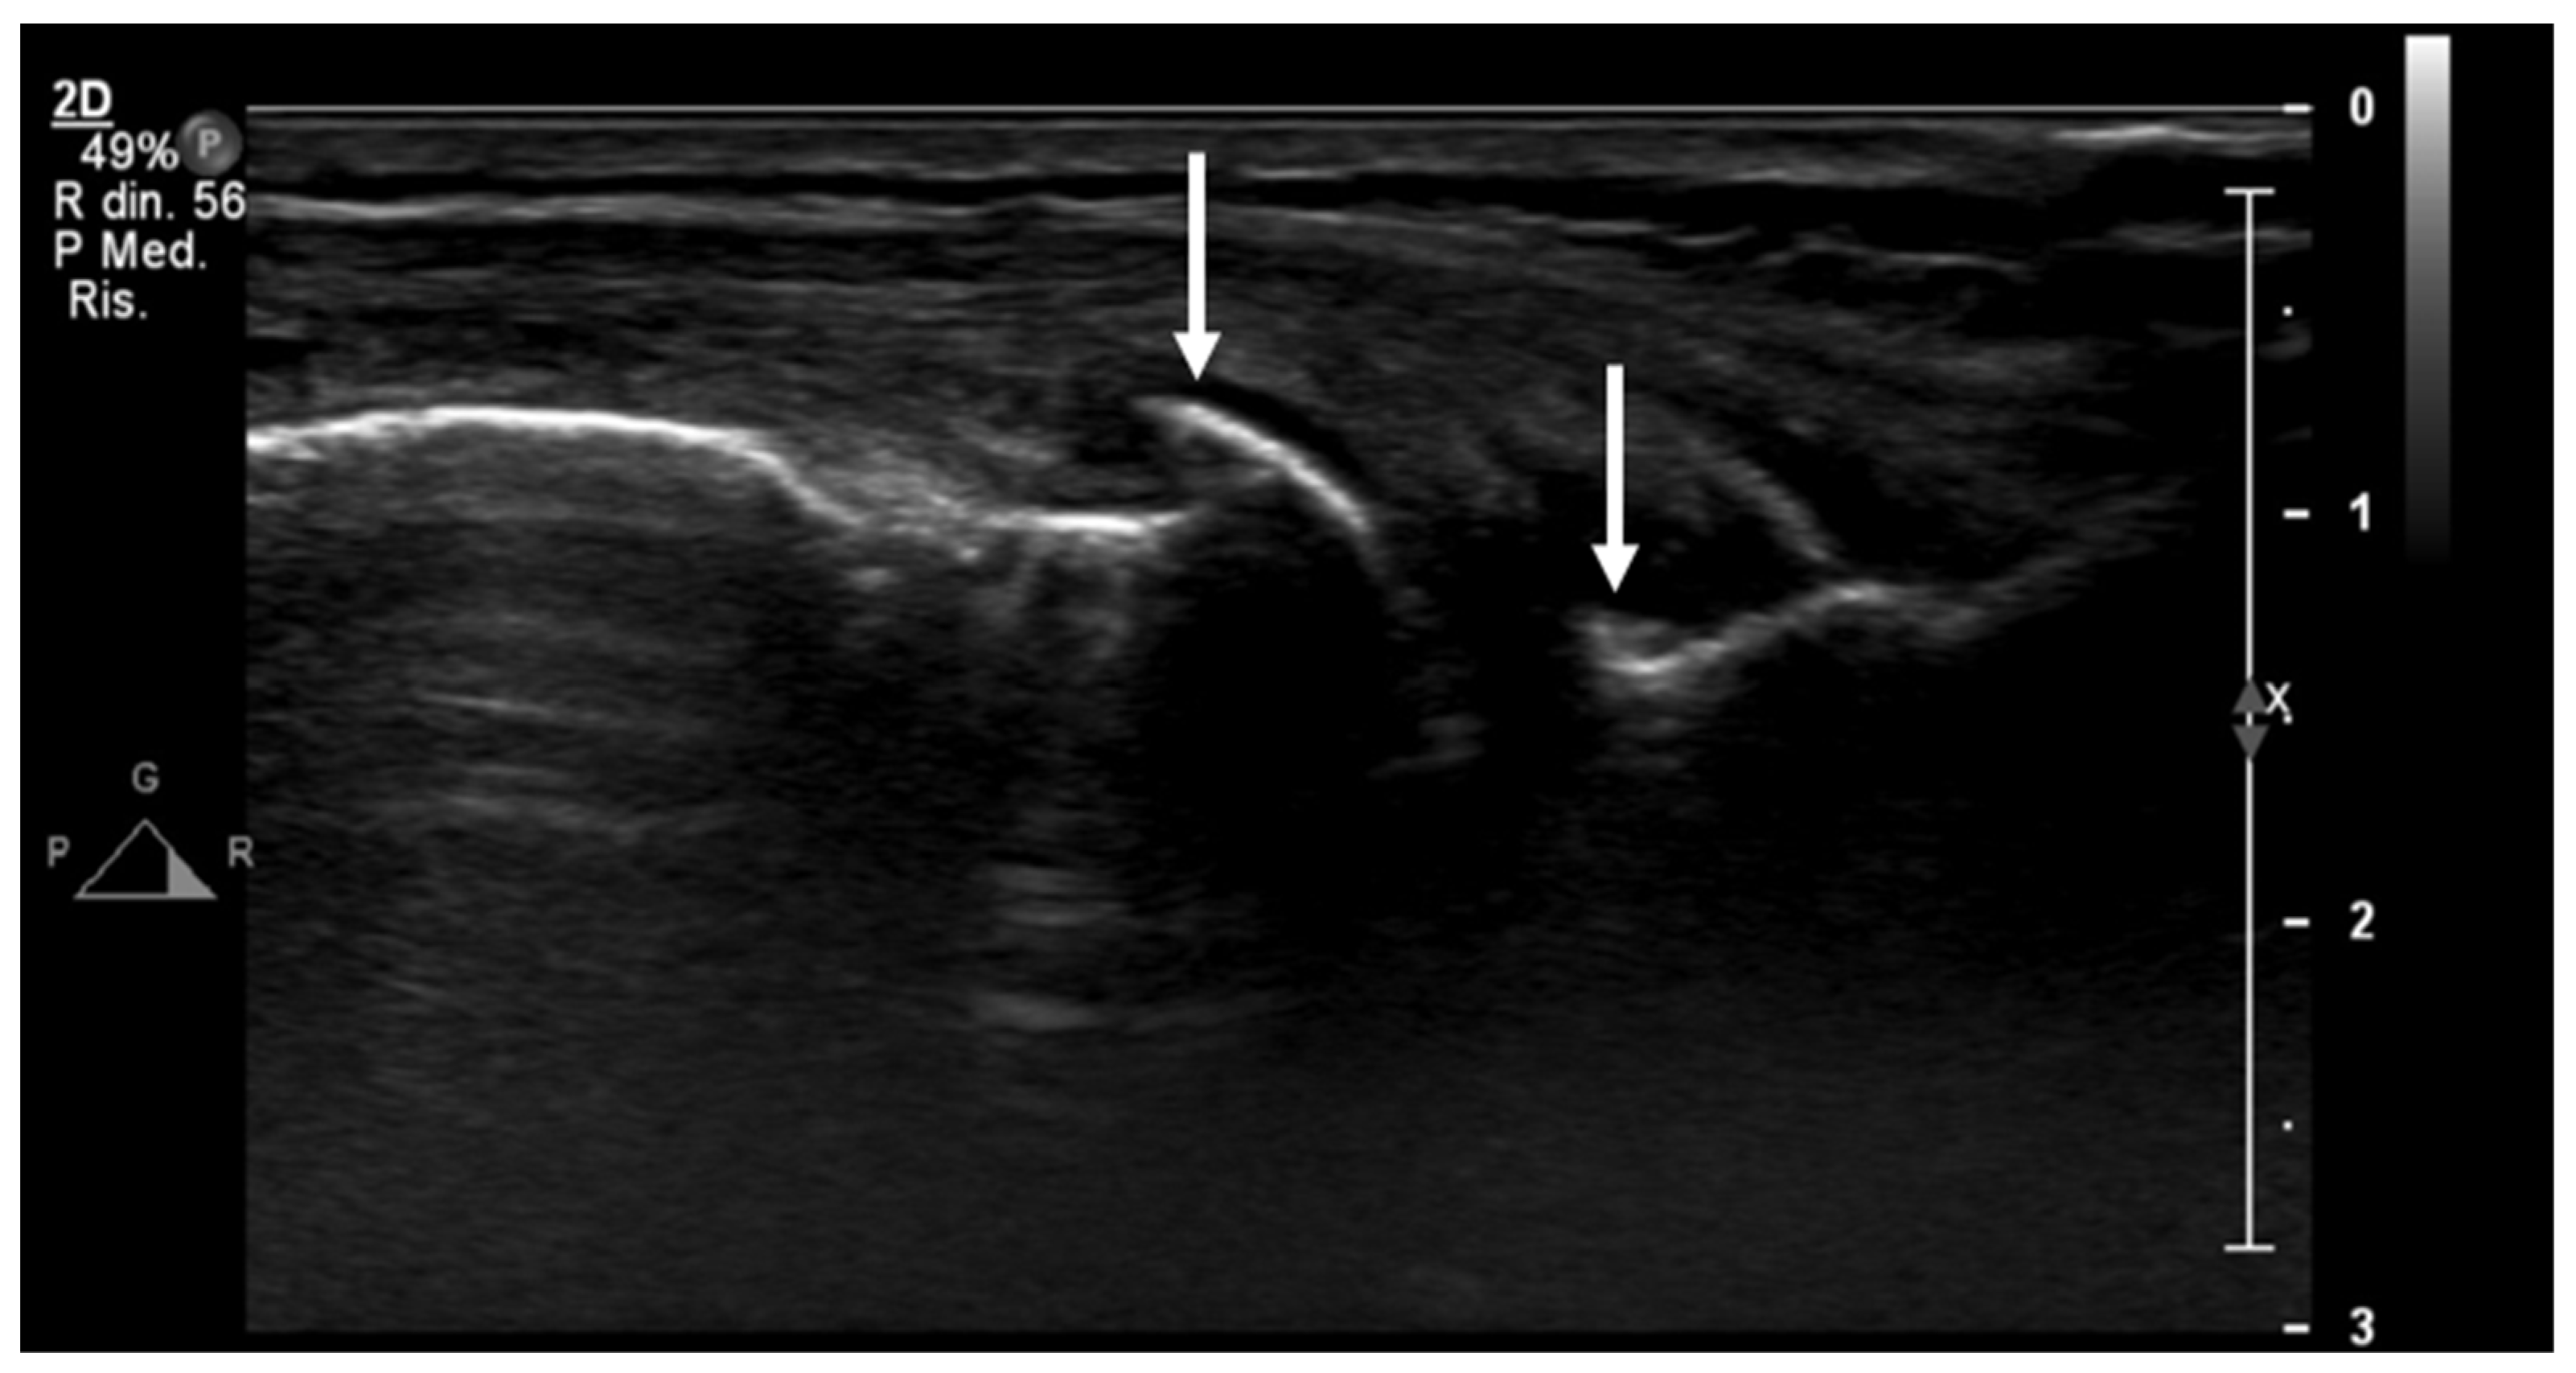

Furthermore, a US is often the first choice for image-guided minimally invasive treatments (e.g., drug injections) in the knee joint due to the wide diffusion and availability of this imaging modality, its low costs, the absence of ionizing radiation, and the possibility of real-time assessment of the needle position (Figure 8).

Figure 8.

Ultrasound-guided intra-articular lateral needle (20 Gauge—arrow) approach into a suprapatellar recess distention (blue line) with abundant joint fluid collection (asterisk) in a patient with knee osteoarthritis. Fluid aspiration and corticosteroid injection have been performed under ultrasound guidance.